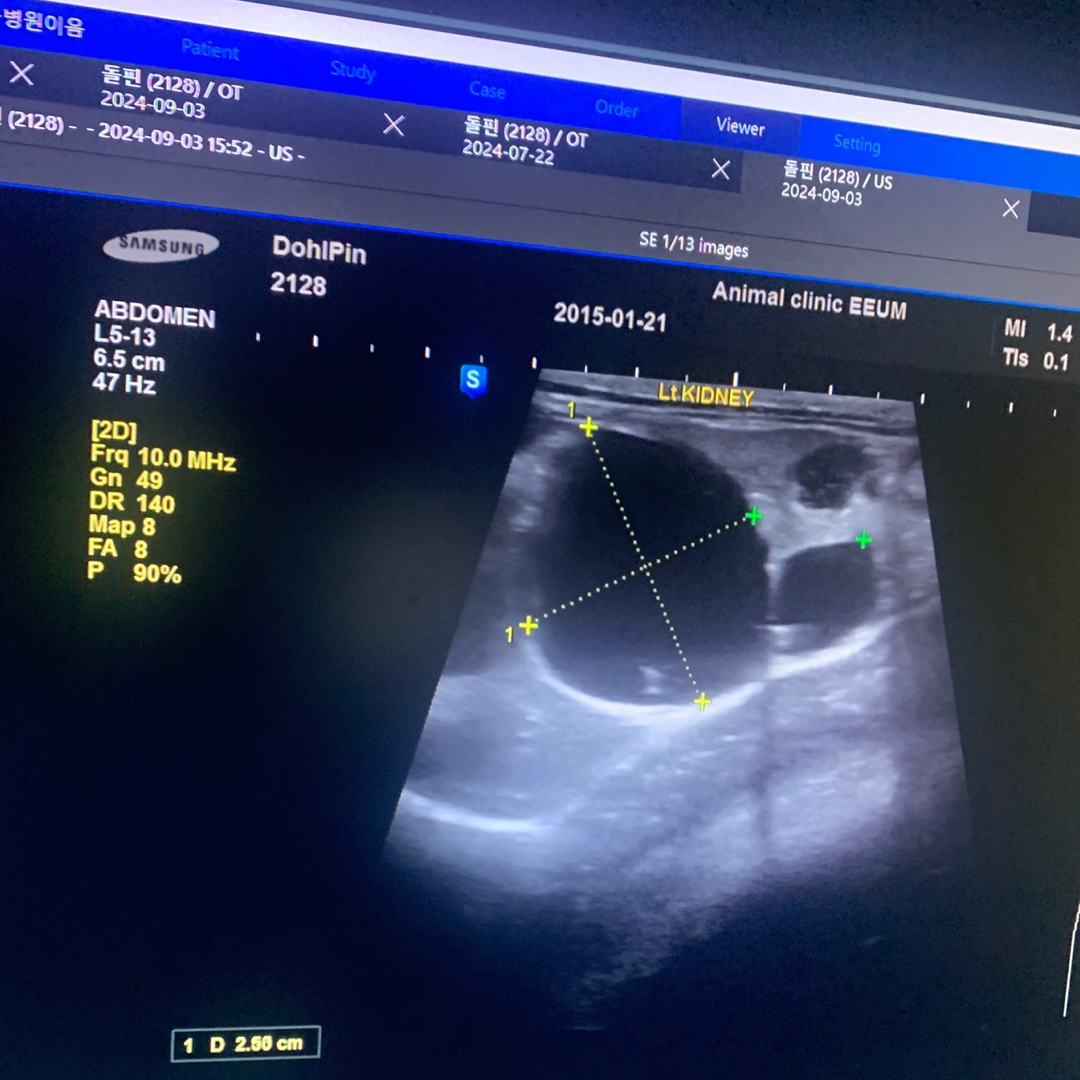

🐈 돌핀(9세, 2.3kg)은 다낭성 신부전(PKD)뿐만 아니라 과민성 대장 증후군, 관절염을 함께 앓고 있는 고양이 입니다. 돌핀은 AIM 활성화를 목표로 '닥터토루 프로토콜'을 3개월 동안 꾸준히 섭취했고, 이 기간 동안 초음파 검사를 통해 왼쪽 신장의 낭종 크기가 2.5cm에서 1.5cm로 감소하는 것이 확인되었습니다. 또한, 활력이 증가하여 이전에는 잠만 자던 돌핀이 다양한 의사 표현을 하며 간식과 사료를 자주 조르는 등의 변화를 보였습니다.